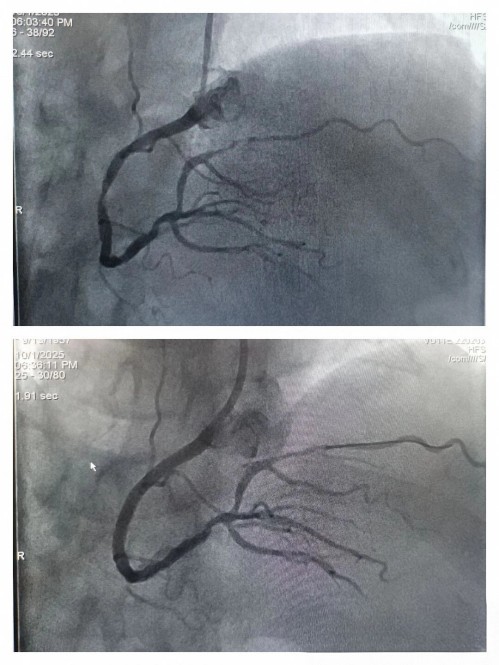

第一位患者右冠植入一枚支架

第二位急诊患者血栓抽吸后

继续药物治疗